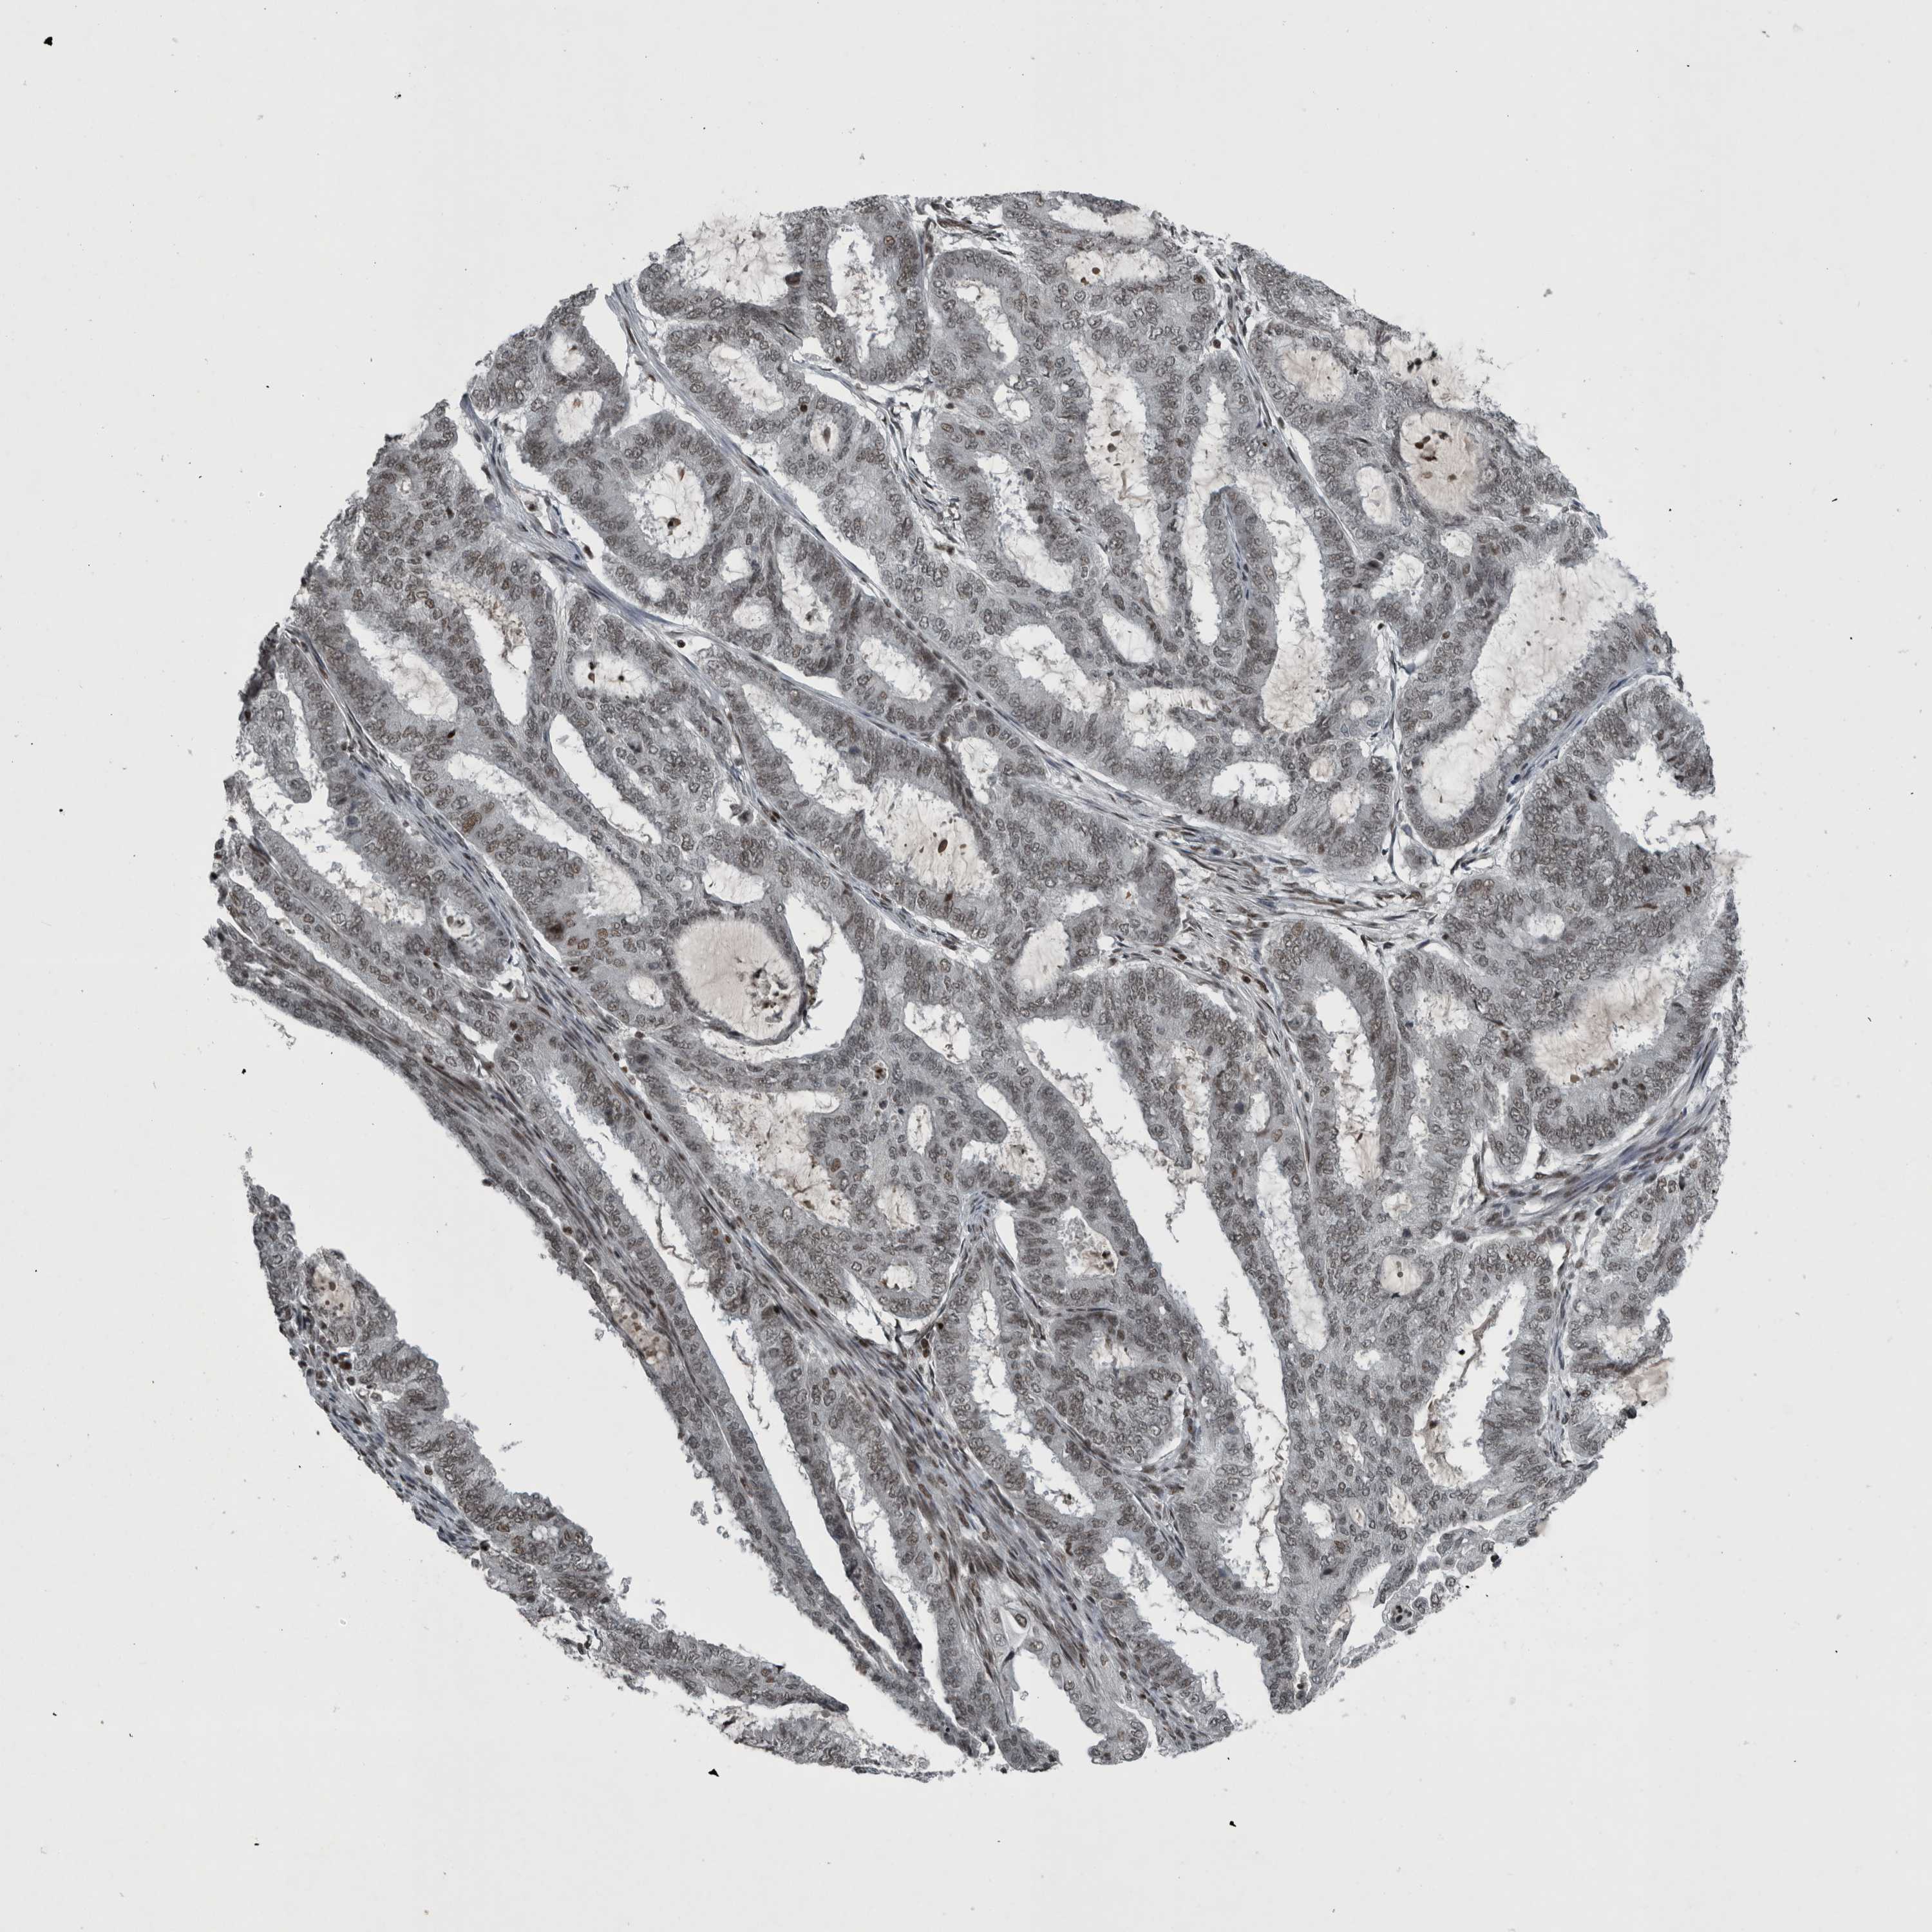

ENDOMETRIAL CANCER - Protein expressioni

A mouse-over function shows sample information and annotation data. Click on an image to view it in a full screen mode. Samples can be filtered based on level of antibody staining by selecting one or several of the following categories: high, medium, low and not detected. The assay and annotation is described here.

Note that samples used for immunohistochemistry by the Human Protein Atlas do not correspond to samples in the TCGA dataset.

Antibody stainingi

Antibody staining in the annotated cell types in the current human tissue is reported as not detected, low, medium, or high, based on conventional immunohistochemistry profiling in selected tissues. This score is based on the combination of the staining intensity and fraction of stained cells.

Each image is clickable and will lead to virtual microscopy that enables deeper exploration of all samples and also displays staining intensity scores, fraction scores and subcellular localization as well as patient and tissue information for each sample.

Antibody HPA027009

Staining

High

Medium

Low

Not detected

Intensity

Strong

Moderate

Weak

Negative

Quantity

>75%

75%-25%

<25%

None

Location

Nuclear

Cytoplasmic/membranous

Cytoplasmic/membranous,nuclear

Adenocarcinoma, NOS

Adenocarcinoma, metastatic, NOS